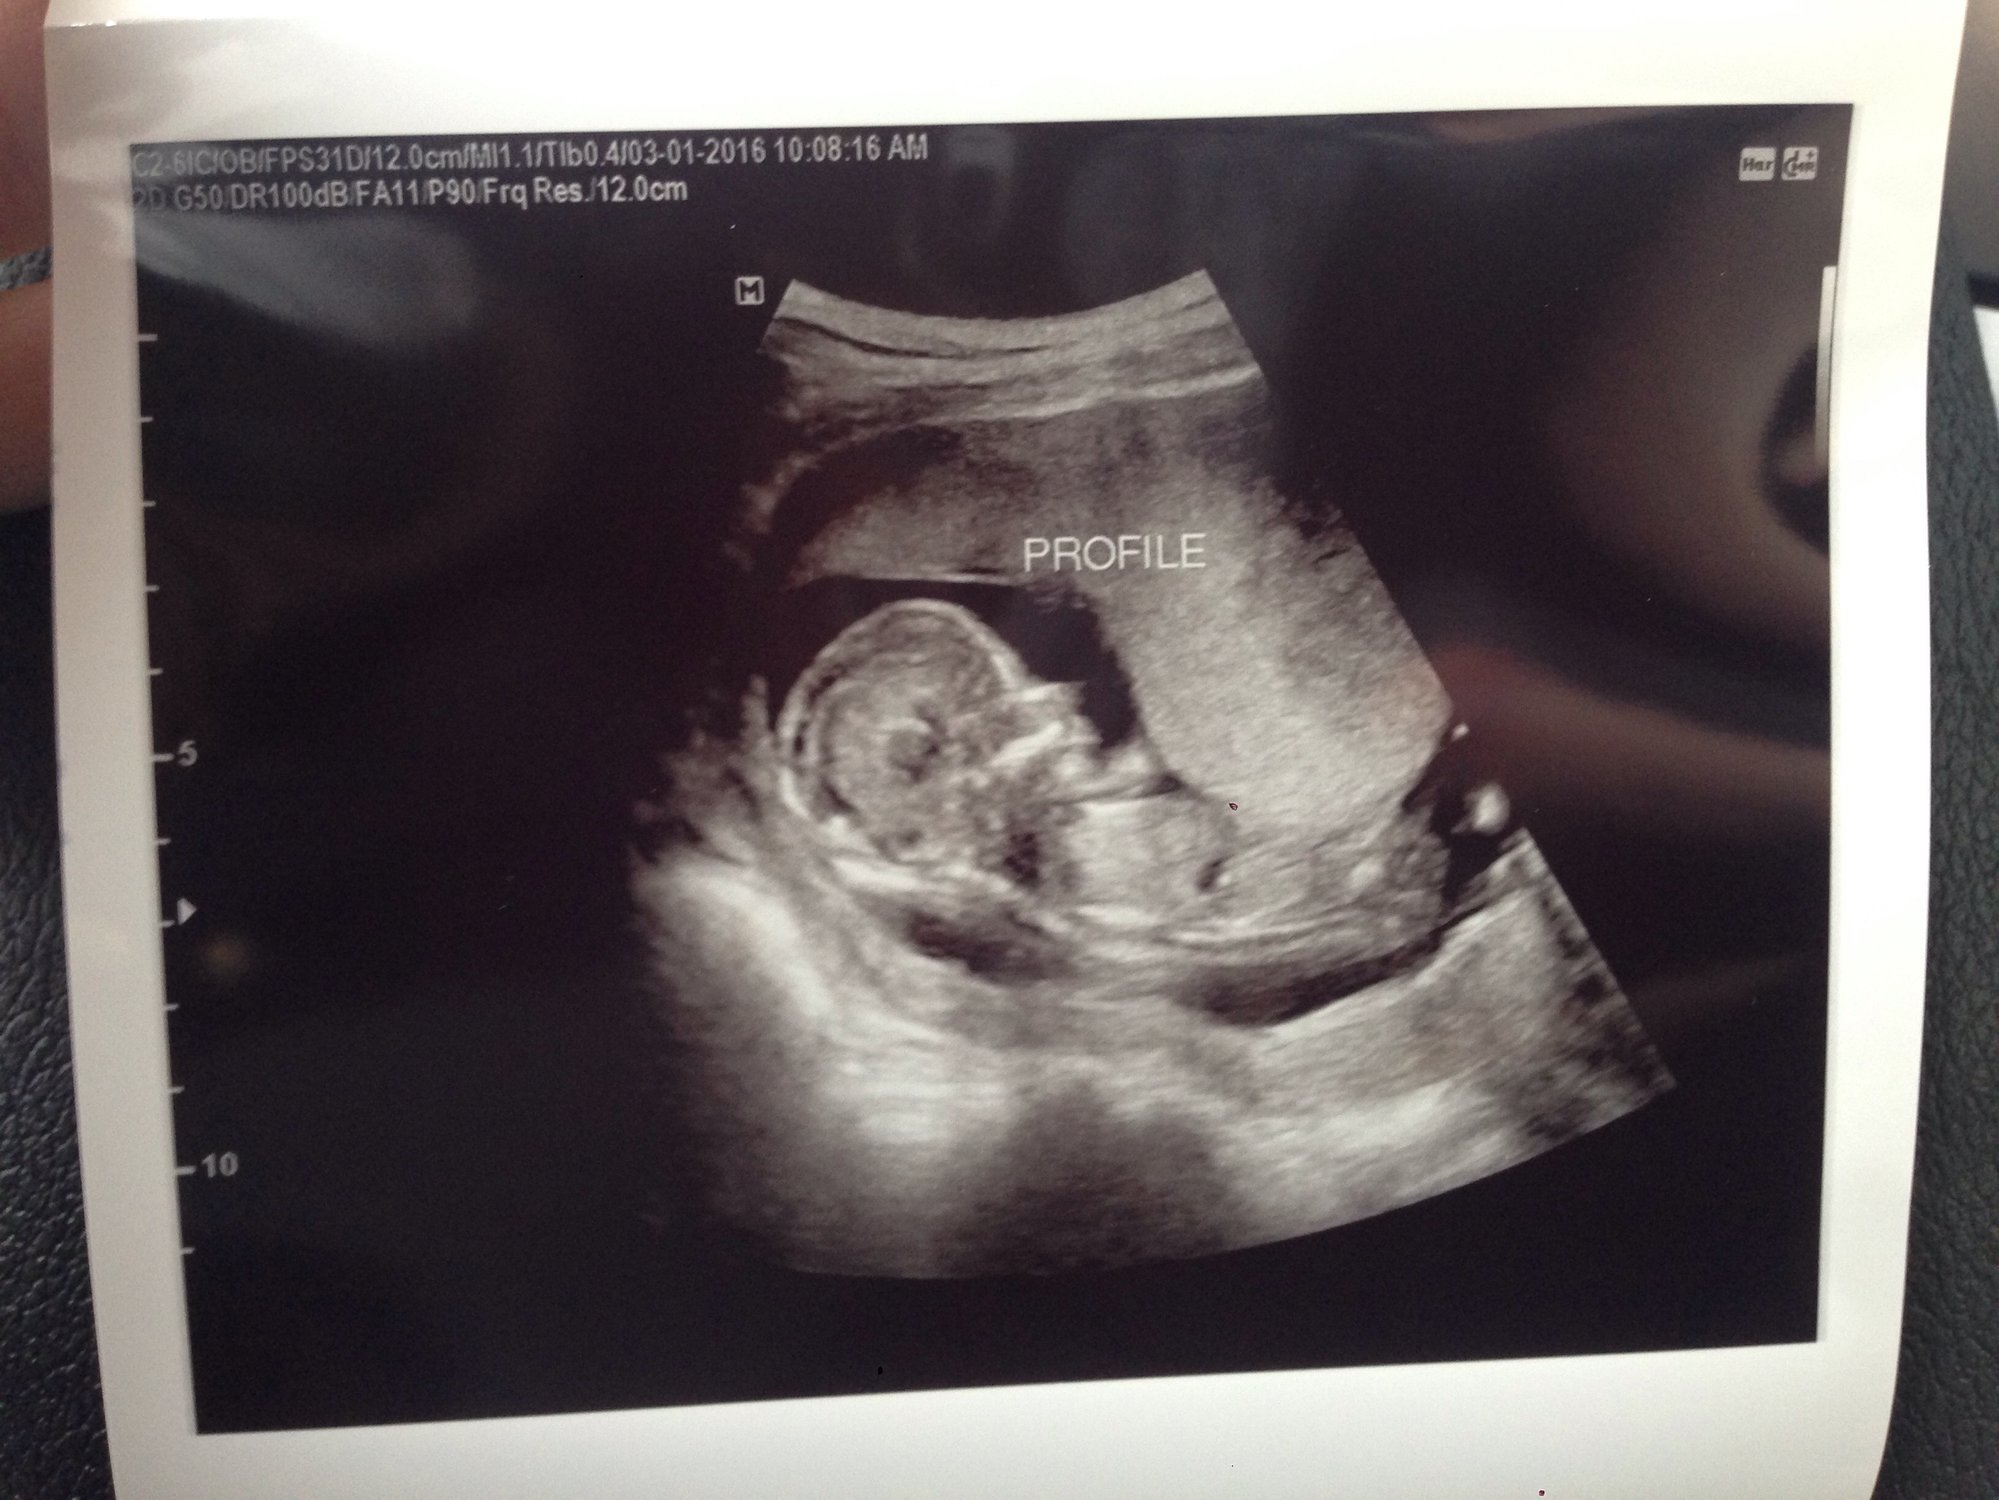

had my 12 week appointment yesterday! baby was moving around so much that it was difficult to get a heartbeat. and then it just showed us it's back side, so no crotch shots to possibly see gender but look at that cute little tooshy!!